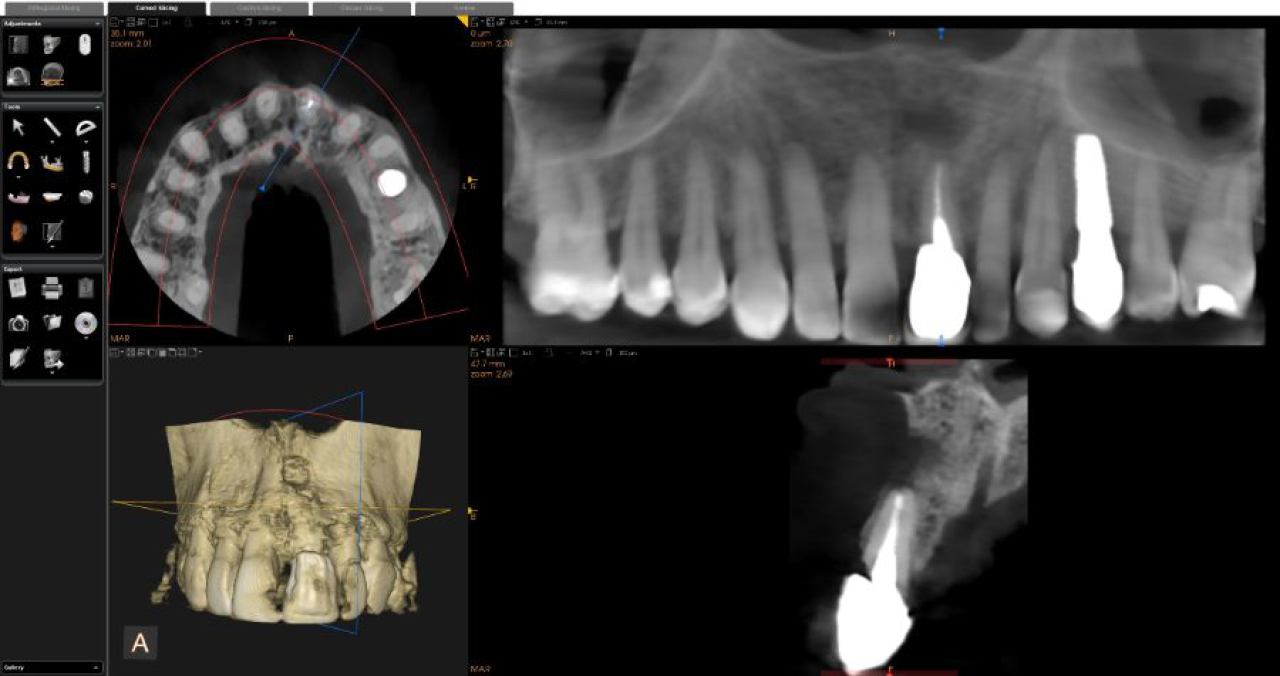

Marković Dental Clinic koristi najmoderniju rendgensku tehnologiju u dijagnostici orofacijalne regije.

Uz minimalnu dozu zračenja pacijenata i maksimalnu zaštitu, rendgenskim snimkama čeljusti možemo analizirati anatomske osobitosti zuba, čeljusti, patološke procese i tvorbe te visinu i širinu kosti čeljusti za planiranje dentalnih implantata.